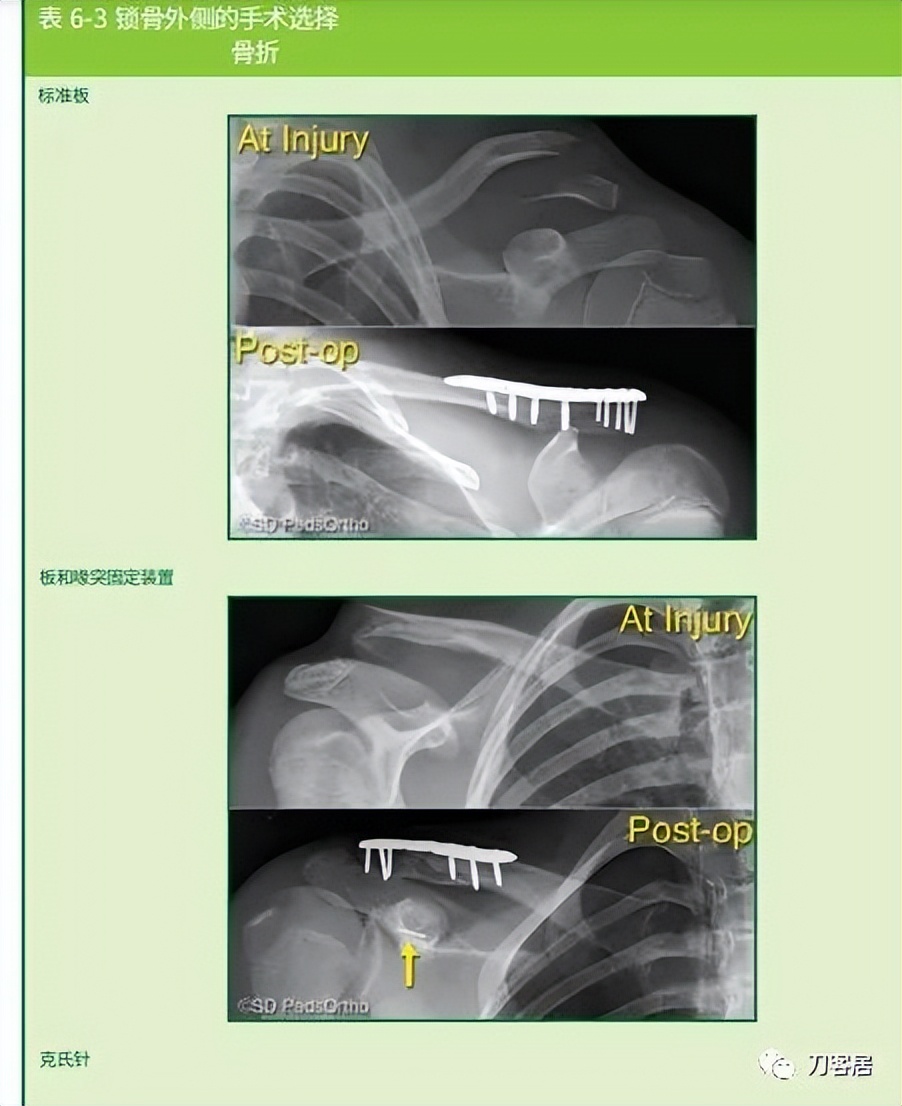

When surgical fixation is potentially required (Type IV, V, or VI injuries), controversy exists as to the optimal fixation technique with some favoring Kirschner wires, others hook plates, pre-contoured lateral clavicle plates, coracoclavicular fixation devices, or a combination thereof (Table 6-3). In the rare circumstance where pin fixation is used, we advocate significantly bending the pin outside the skin to minimize wire migration and weekly clinical evaluations until the pins have been removed (typically 3-4 weeks). The literature indicates that there can be significant complications from pin migration, including death. We believe each of these cases must be approached on an individual basis based on the size and comminution of the fracture fragments.

当需要手术固定时(IV、V或VI型骨折),采取何种固定技术存在争议,有人喜欢用克氏针,另有人喜欢钩板、预弯外侧锁骨板、喙锁固定装置或它们的组合(表 6-3)。在罕有的髓内针固定时,我们主张将针的一端折弯留置皮肤外侧,以防固定针移位,并且每周随访直至固定针去除(一般需要 3-4 周)。文献表明,固定针移位可能会导致严重的并发症,甚至死亡。我们认为,每个病例都应该根据骨折粉碎程度以及骨折块的大小,遵循个体化治疗原则,决定治疗方案。